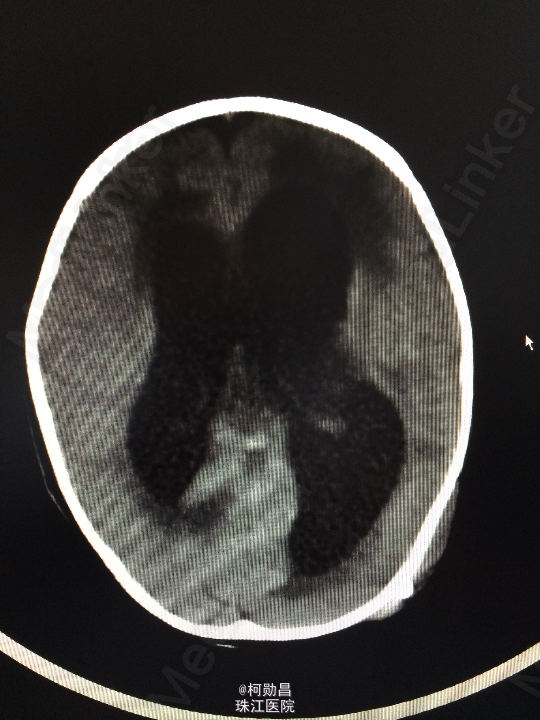

查体:神志不清,四肢肌力增高 辅助检查:头颅CT提示脑积水并脑脊液外渗,幕上脑室扩张,右侧额颞叶硬膜下脑脊

诊断:化脓性脑膜炎伴脑积水 处理:予内科抗感染治疗,后行脑室腹腔引流术。